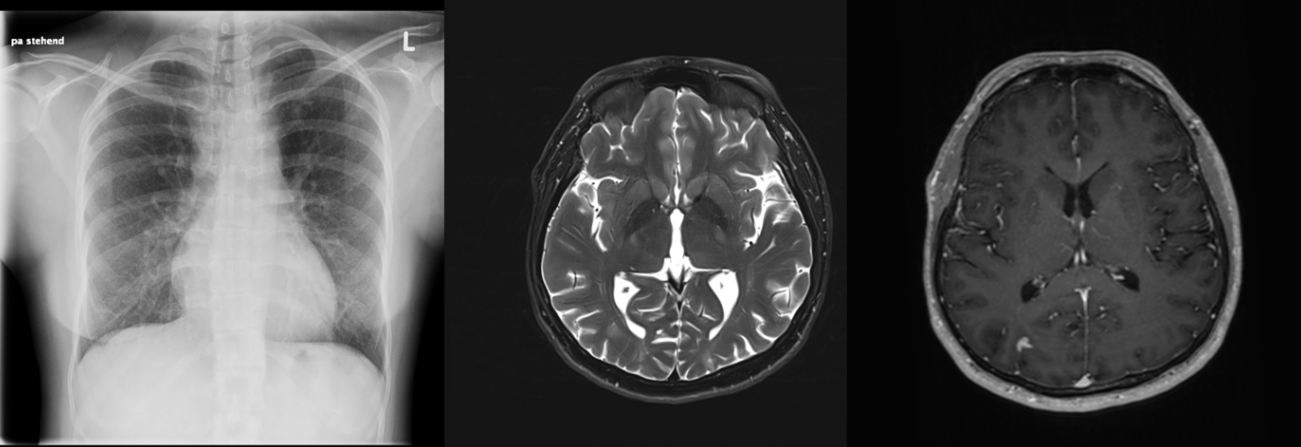

Bei der klinischen Untersuchung zeigte sich ein ubiquitär abgeschwächtes Atemgeräusch sowie eine Tachypnoe. Neurologisch zeigte sich eine brachiofazial betonte Hemiparese rechts mit einer Kraftminderung von 3/5 des rechten Armes. Die Kardiotokographie (CTG) des Kindes zeigte sich unauffällig. Ein Notfall-MRT des Kopfes wurde veranlasst. Da die initiale Röntgenaufnahme des Thorax sich pathologisch zeigte, wurde eine Computertomographie des Thorax zusätzlich durchgeführt.

Die Röntgenthorax- sowie die Computertomographieaufnahmen zeigten eine Disseminiert-fleckförmige Konsolidierung der gesamten Lunge mit miliarem Muster.

Die cMRT zeigte intrakraniell disseminierte, KM-enhancende Läsionen, teilweise mit ausgedehntem Perifokalödem und Diffusionsrestriktionen, sowie occipital und im Sulcus centralis bds. betontes leptomeningeales KM- Enhancement.